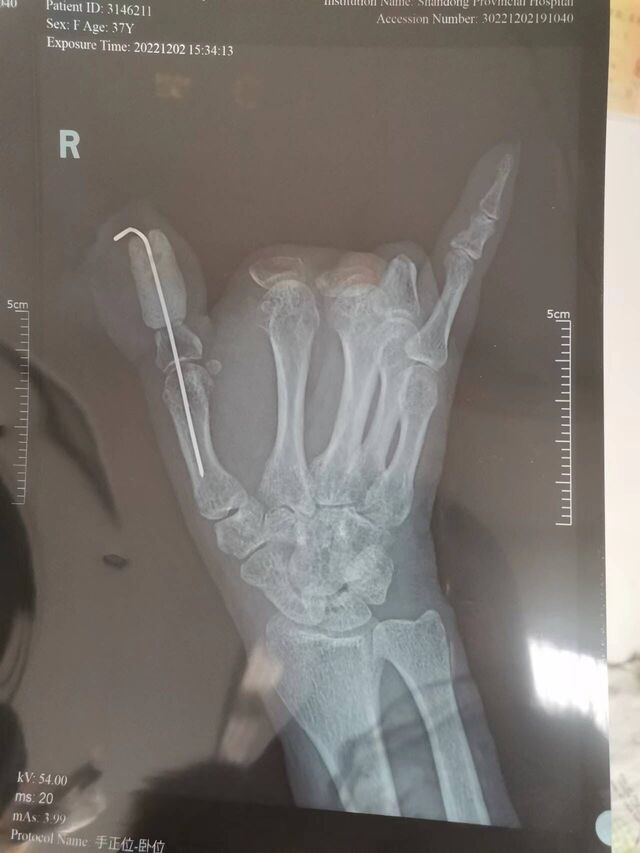

拇示中环指全形再造手指

一例拇示中环指4个长手(拇)指全形再造,足趾全部保留。该病例入选WSRM最佳病例竞赛决赛。